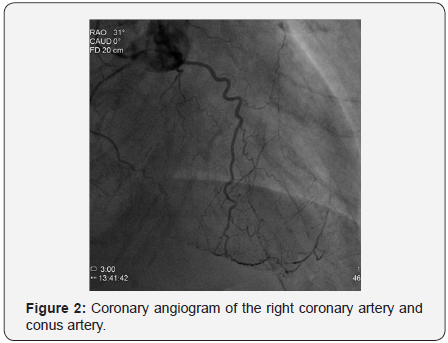

The patient was 87 years old male with a history of hypertension, type two diabetes mellitus presenting with shortness of breath progressively ending into respiratory distress over two days before admission to our department, the patient had a history of chronic kidney disease stage 3, serum creatinine was 1.68mg/dl on admission which became 2.23mg/dL thereafter, and positive Toponin I at admission, electrocardiogram showed sinus tachycardia with minimal ST depression at inferolateral leads, minimal ST segment elevation at V1-V4 with pathological Q waves, chest x-ray showed pulmonary edema, under impression of NSTEMI he was admitted and scheduled for an angiogram which showed severe triple vessel coronary artery disease with heavy calcifications of left system as illustrated in Figures 1 & 2; the proximal left anterior descending artery (LAD) had severe stenosis 93%, the mid left anterior descending artery (LAD) had chronic total occlusion (CTO) after giving a large septal branch and second diagonal (D2), collaterals to CTO segment from distal left circumflex artery (LCx) Grade 1/3; p-LAD bridging collaterals Grade 1/3 and large epicardial tortuous collateral from conus branch to distal LAD Grade 3/3, the proximal left circumflex artery (LCx) was acutely angled tortuous vessel with heavy calcifications showing proximal stenosis 74%, and the right coronary artery (RCA) was small non-dominant diffusely diseased vessel (Syntax score: 39.5), Echocardiogram showed borderline left ventricular performance with resting wall motion abnormalities, dyspnea then progressed, and acute respiratory distress developed that necessitated respiratory support with mechanical ventilation and hemodynamic support with intra-aortic balloon pump (IABP).